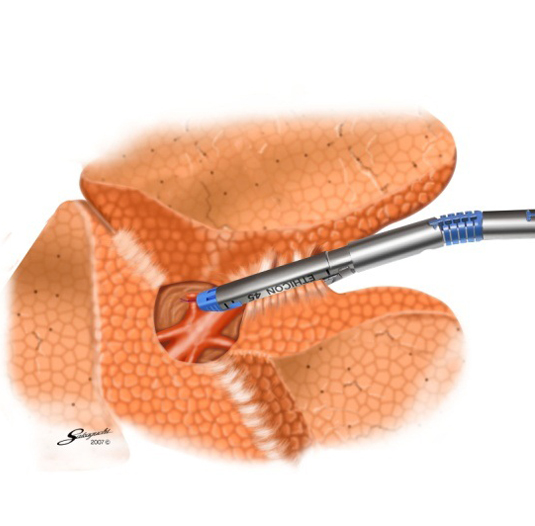

胸腔鏡手術の実際(右肺上葉切除時の自動縫合器使用例)

葉間切離

術中写真自動縫合器による肺嚢胞(ブラ)切除(肺部分切除)

肺嚢胞

自動縫合器による肺切除

肺切除後の状態